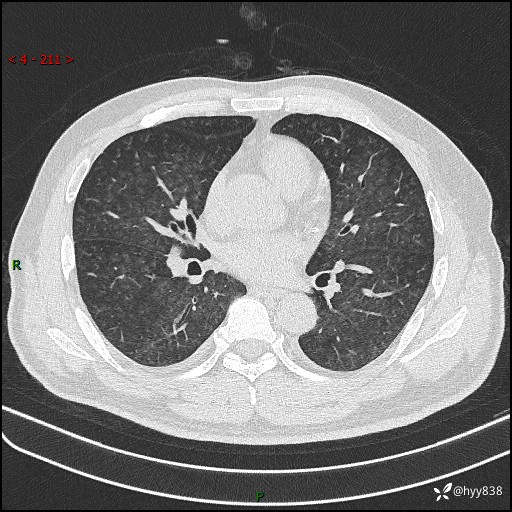

辅助检查:CT

胸部HRCT